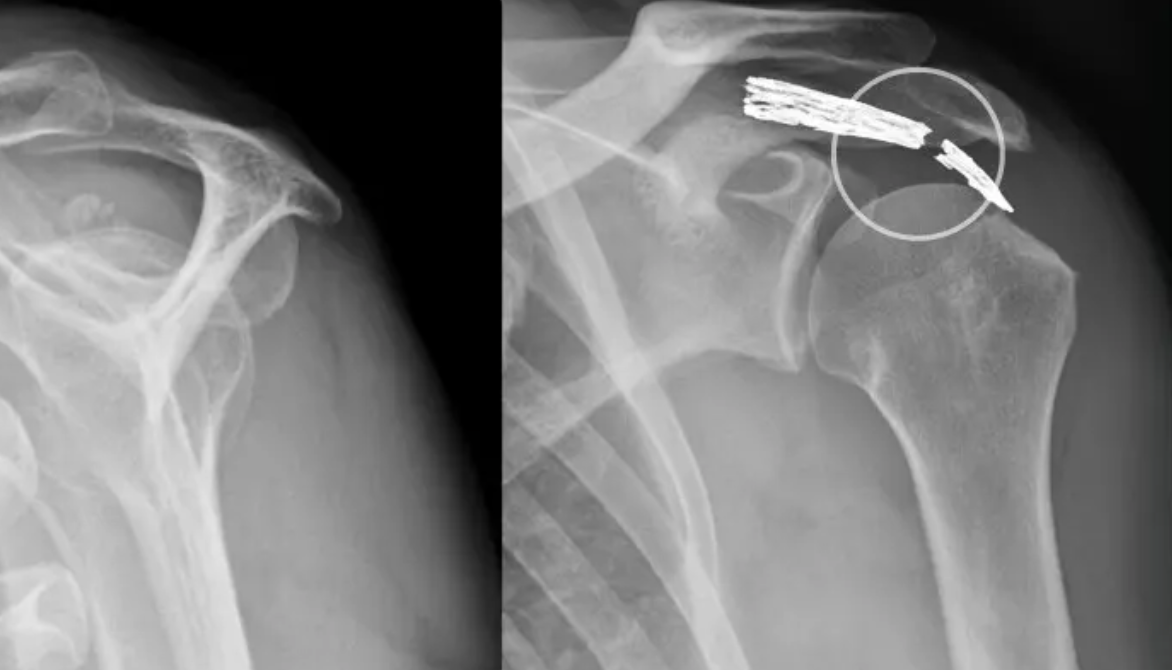

- SLAP Läsion: Je nach Ausmaß der Verletzung wird der Bizepsanker entweder geglättet oder mit einer Naht wieder an der ursprünglichen Position fixiert.